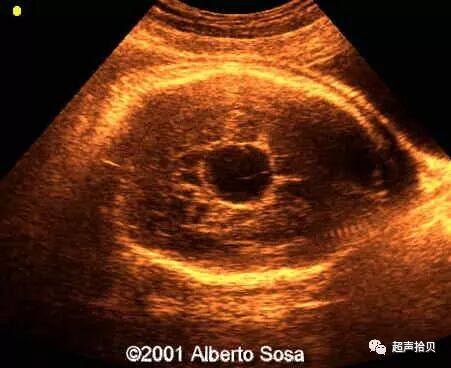

图2:冠状超声图显示位于后颅窝蛛网膜囊肿